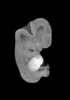

MRI Slice Selector

Mouse: click on a line below to select a view

Finger: tap a line below with a very light touch